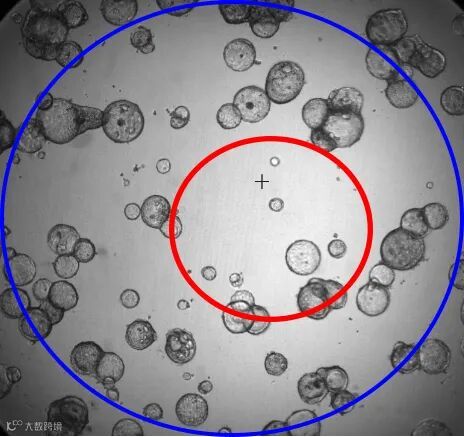

背景明暗不均,单一阈值设置无法对背景有效界定(红色区域内亮度高,蓝红交接处亮度明显下调)。

细胞球灰度值和背景太接近,筛选阈值设的低则部分背景被识别,筛选阈值设的高则部分细胞球不能被识别。

细胞球相互靠近,分析时总是不能准确识别单个细胞球。